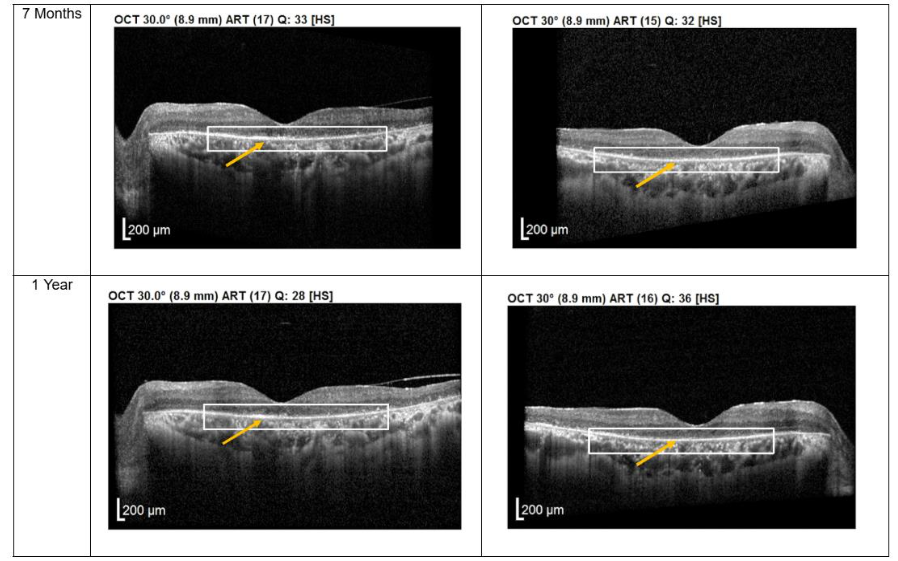

Both patients received a total of seven mesenchymal stem cell (MSC) transplantations, administered every 4-6 weeks, with follow-up from November 2020 to November 2022. Both patients reported no deterioration in vision since the first subtenon implantation in November 2020. Optical coherence tomography (OCT) images consistently demonstrated the maintenance of a hyperreflective region, with no notable increase in intensity. The previously reported improvements in visual function remained stable throughout the two-year follow-up, with no evidence of regression.

Figure 1. Optical coherence tomography (OCT) images for both eyes of Patient 1 from pre-injection up to 1 year follow-up. Orange arrow demonstrates the presence of hyperreflective material at the interdigitation area of the photoreceptors at the macula and extramacular region. These were observed and maintained until the last follow-up examination.

Importantly, no severe ophthalmic or systemic complications were observed during this period, supporting the safety of subtenon MSC therapy over a prolonged follow-up. No serious adverse effects were reported by either patient.

Structural changes observed on optical coherence tomography (OCT) provide additional insight into the biological effects of treatment. All patients demonstrated persistent hyperreflective material localized at the interdigitation zone of the photoreceptors. Rather than representing fibrotic change, this OCT finding may reflect photoreceptor outer segment remodeling, improved mitochondrial activity, or enhanced metabolic integrity of surviving photoreceptors. Similar hyperreflective changes have been reported in studies evaluating MSC-mediated neuroprotection and are often associated with functional stabilization rather than disease progression. The stability of these OCT findings over extended follow-up in patients 1 and 2 suggests a sustained therapeutic effect rather than a transient inflammatory response.